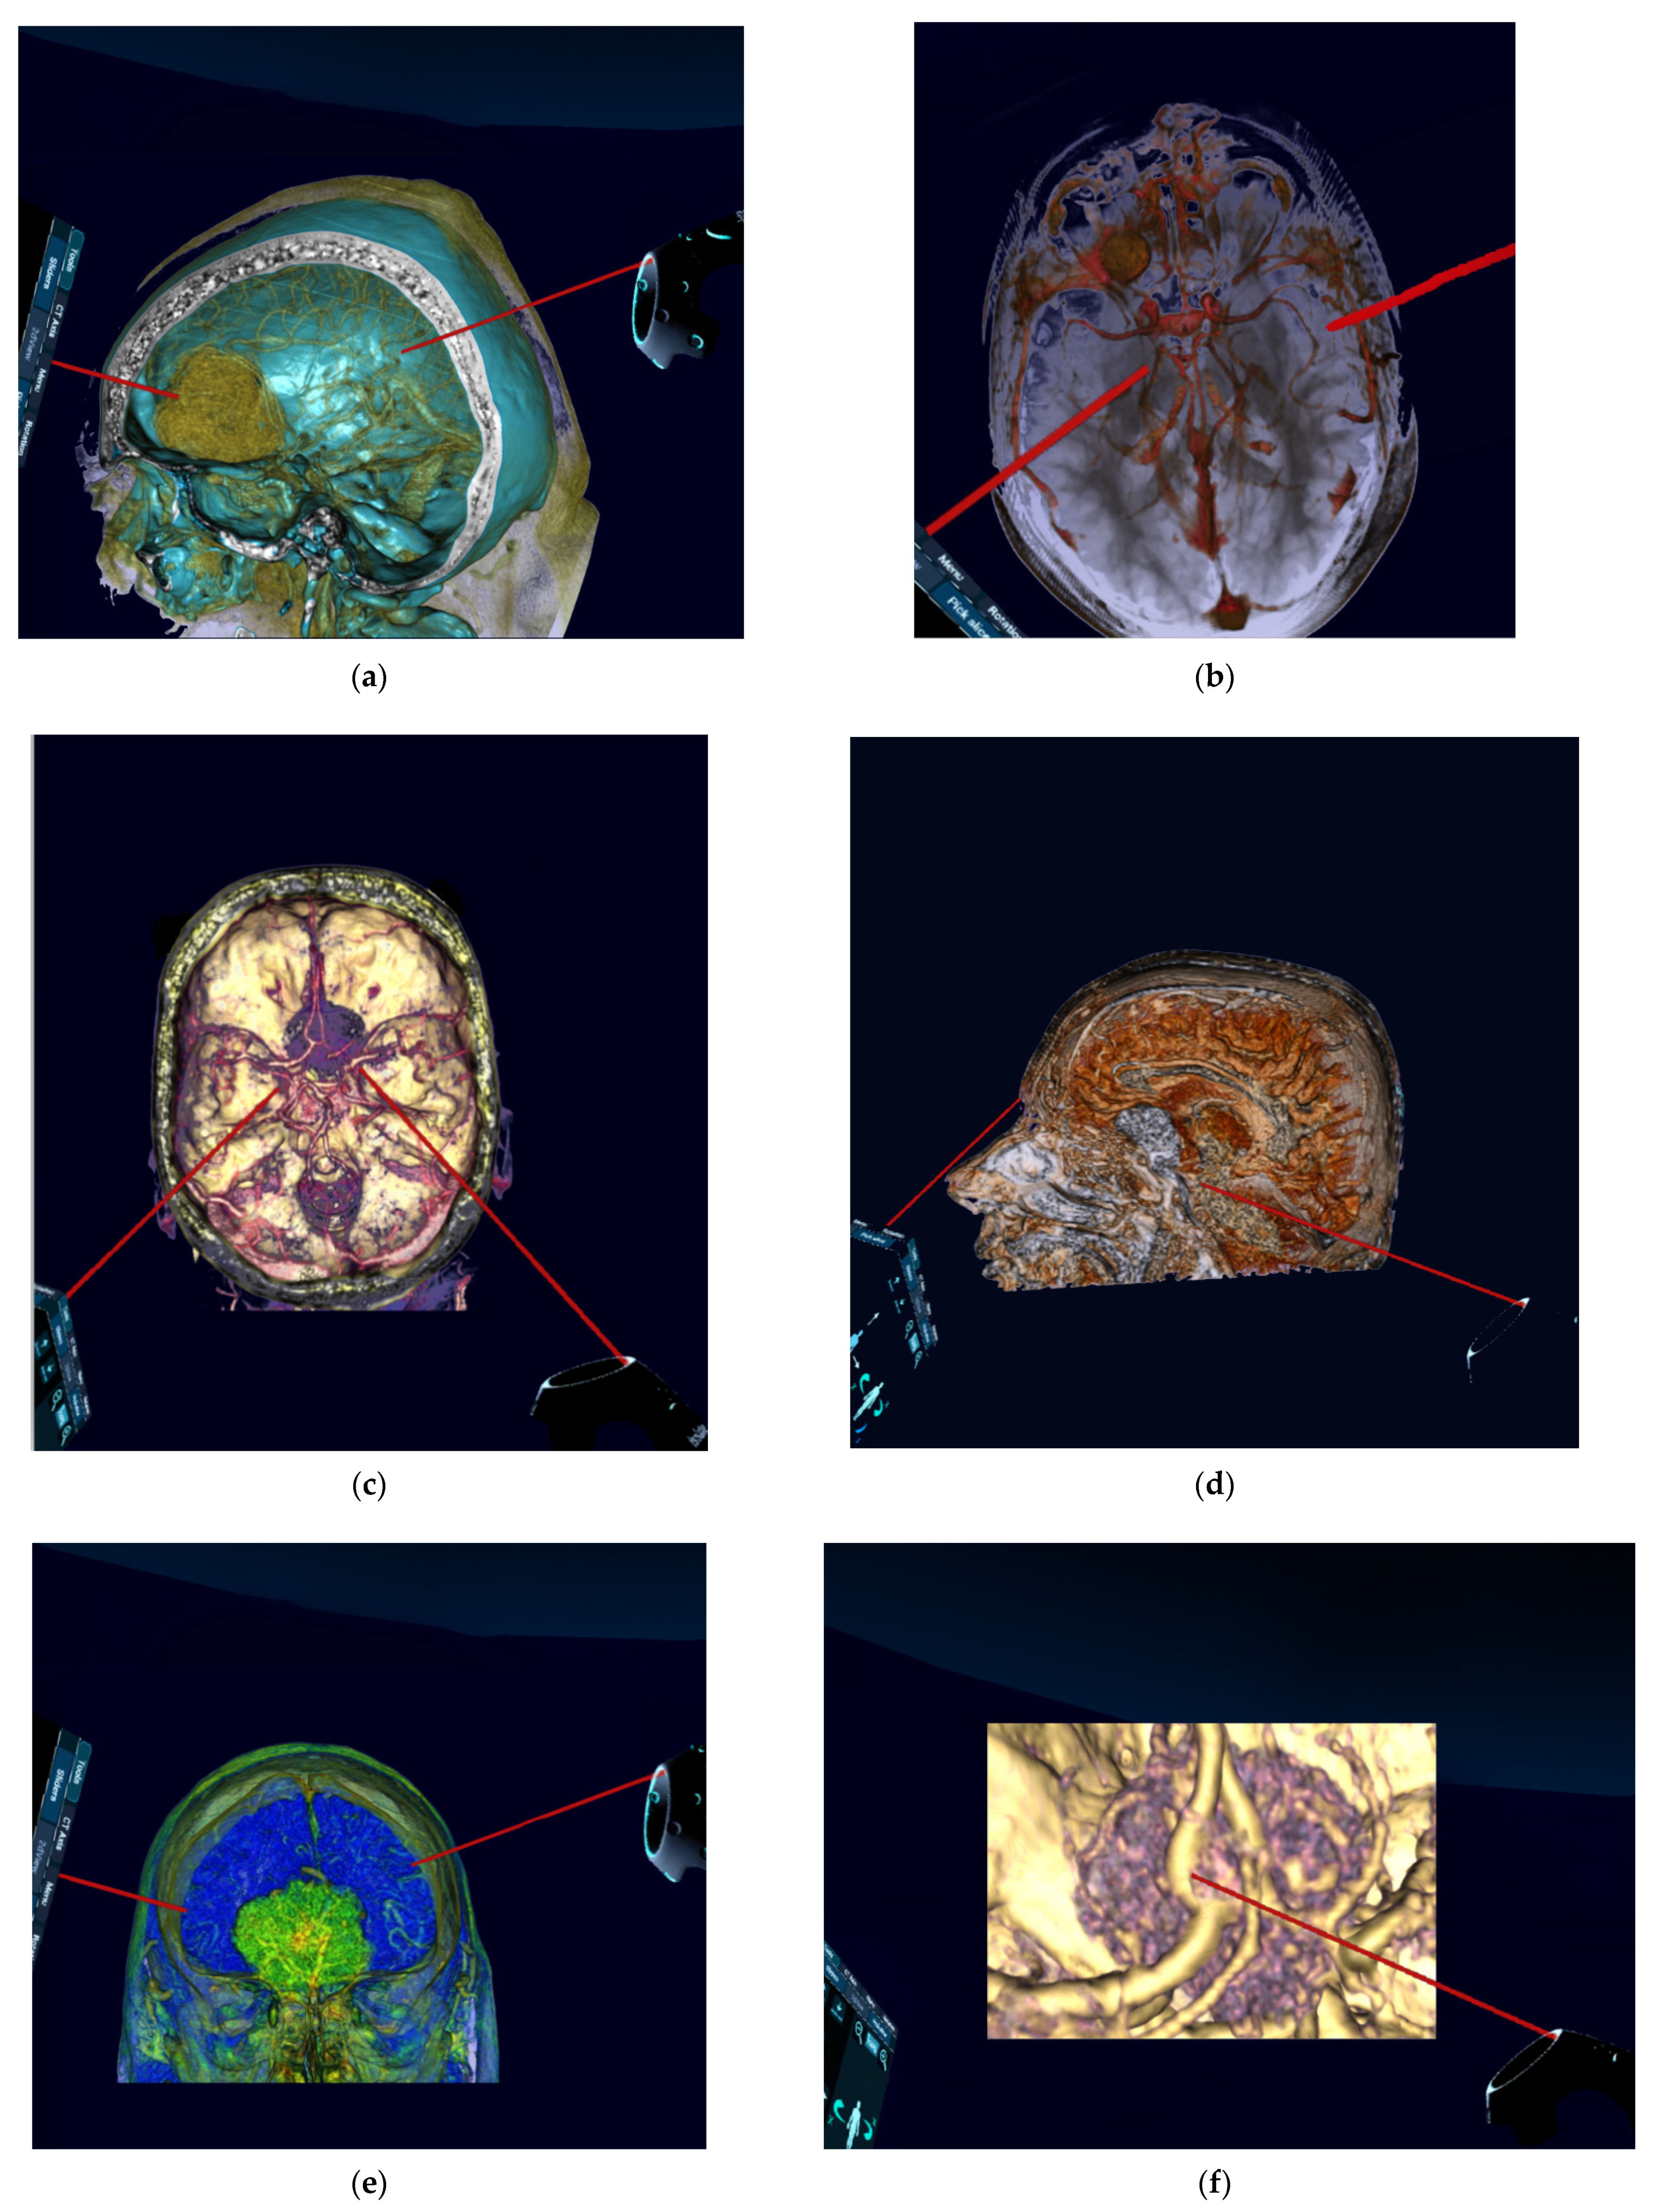

Figure 4. Preoperative reconstructed 3D-virtual reality images (reconstructed from 2D-CT and 2D-MRI) of patients with anterior skull base meningiomas. (a) Oblique lateral aspect showing olfactory groove meningioma. (b) Superior aspect showing frontobasal meningioma. (c) Superior aspect showing planum sphenoidale meningioma. (d) Lateral aspect showing anterior clinoidal meningioma. (e) Anterior aspect showing olfactory groove meningioma. (f) Highly zoomed superior aspect showing planum sphenoidale meningioma. (g) Zoomed superior aspect showing planum sphenoidale meningioma. (h) Zoomed oblique lateral aspect showing olfactory groove meningioma. 2D, two-dimensional; 3D, three-dimensional CT, computed tomography; MRI, magnetic resonance imaging.